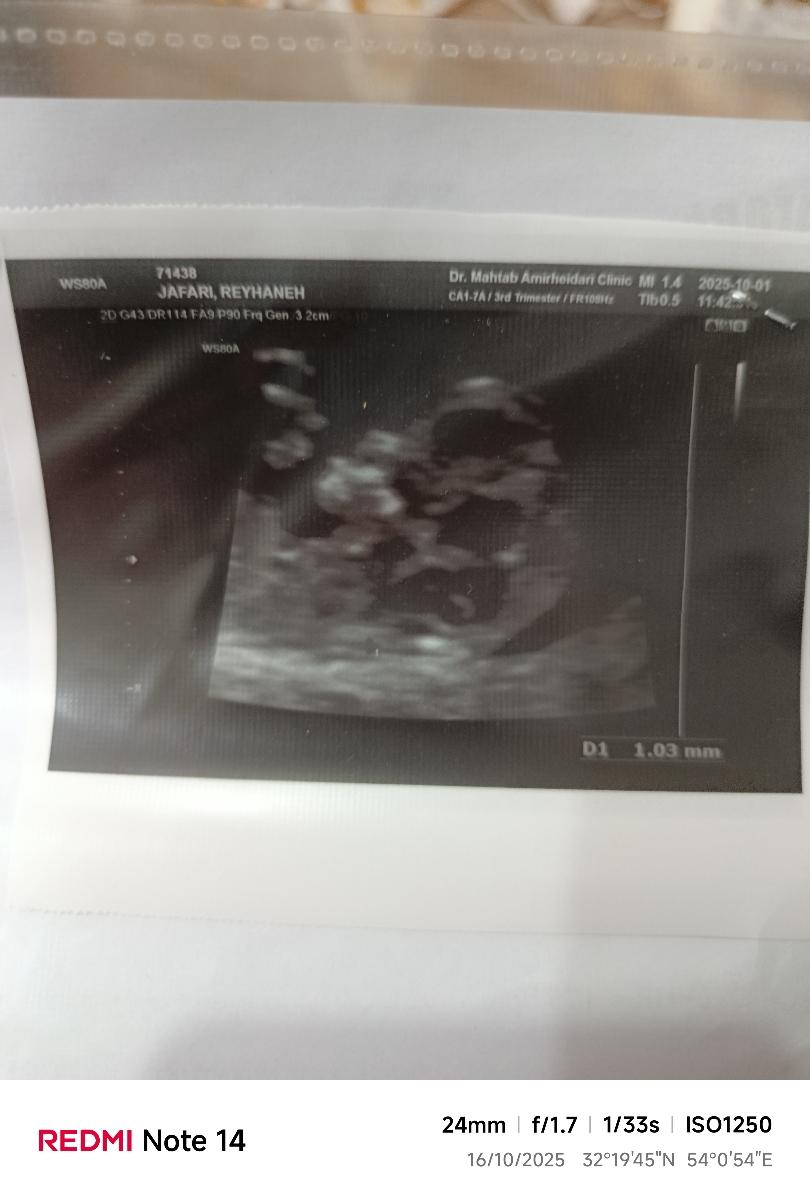

1404/07/21

rihanna jafari

سلام عزیزم هر چی پرسیدم نگف

نه عزیز🥺😔

سونوتوبفرست حدس بزنم

جدی الان میفرستم

عکس جنین

مشخص نیس

فقط سرش

داری مامان یه گل پسردیگه میشی

نه

جدی؟

کاریه🥲

سر کاریه

چطور؟

از کجا متوجه شدی

سرش جوریه که ۴گوشه داره

فکر کردم باهام شوخی میکنی

جدی

خیر سرم زیر نظر دکتر زنان بودم گف دوقلوییش دست من جنسیتش دست من نیس😔 که آخرم یه قل شد

دو هفته دیگه نوبت آنومالی دارم

1404/07/25

دختره نی نی

جدی عزیزم؟

از کجا متوجه شدین گلم؟

خدا کنه سالم باشه و دختر😍😍😍

از فرم جمجه اش کپی عکس ان تی دخترمه

عزیزم بخدا کلی امیدوار شدم 😍😍😍 مرسیییییییییی

این برا قلبش رفتم

اینم برا انتی

0

اینم ان تی

علایم م پسره ولی حسم دختره

انگاری پسره برا شما

به پسرمیخوره